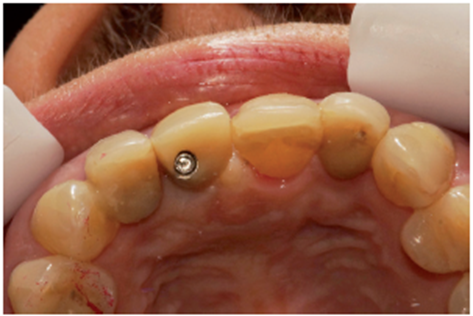

Após quatro meses foi realizado o segundo tempo cirúrgico com fresa cilíndrica diamantada, acessando somente o Cover Screw (Figura 22). O Cover Screw foi removido com a chave de 1.2 (Figura 23), um cicatrizador foi instalado (Figura 24) e o provisório foi reposicionado.

Na consulta seguinte, o cicatrizador foi removido e através do Kit de seleção de componentes, o pilar protético foi selecionado. O pilar de escolha foi o Ideale 3.3 x 4.0 x 1.5 angulado de 30 graus. Neste momento foi realizada uma moldagem com transferente de moldeira fechada (Figuras 25 e 26) para copiar o posicionamento tridimensional do implante e o modelo de trabalho foi obtido.

No laboratório, o técnico de prótese posicionou o pilar Ideale angulado no modelo (Figura 27) e confeccionou um incisivo central parafusado sobre ele, utilizando a coifa de provisório que o sistema oferece (Figura 28). Uma vez obtido o provisório, o cicatrizador voltou a ser removido e o pilar Ideale e o provisório foram instalados em boca (Figuras 30 e 31). O pilar foi torqueado em 20 Ncm e o parafuso da coroa foi torqueado em 10 Ncm. Após 15 dias, o provisório foi removido e observou-se o perfeito perfil de emergência que havia sido obtido (Figura 33). Neste novo momento foi posicionado sobre o pilar um transferente plástico de moldeira fechada do pilar Ideale, sendo que tanto o pilar como o dente 12 foram moldados (Figura 34) para a confecção de copings e posterior a aplicação da cerâmica (Figura 35).